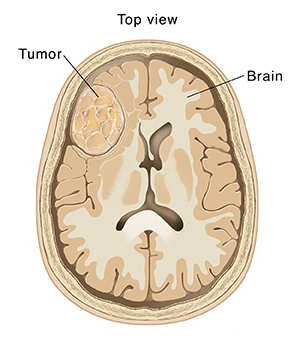

Brain Tumors

A brain tumor is a mass of abnormal cells in the brain. There are many types of brain tumors. They may start in the brain (primary tumors) or travel to the brain from another part of the body (metastatic tumors). Brain tumors may be slow growing, not likely to spread, and not cancer (benign). Or they may be quick growing, cancer (malignant), and able to spread to other parts of the brain. Both kinds of brain tumors, benign and malignant, can cause serious problems by pressing on and damaging normal brain tissue. Symptoms will depend on the type of tumor, how big it is, and where it is in the brain.